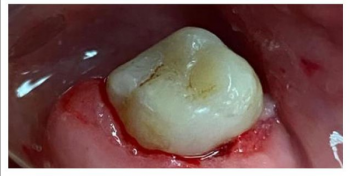

Равиля Равилевна: «Ваша улыбка – показатель здоровья и благополучия. Не даром говорят глаза – зеркало души, а зубы – зеркало здоровья. Цель моей работы – здоровые и красивые зубы пациента. А лучшая награда, когда пациент и окружающие его люди не могут отличить леченый мною зуб от родного здорового!»